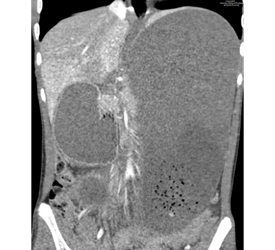

We selected this case because of its unique presentation and associated findings. The patient’s medical managing team was surprised when we communicated to them the finding of suspected gastric outlet obstruction on abdominal radiograph and recommended placement of an enteric tube with order for immediate cross-sectional imaging. They told us that the working diagnosis was constipation and were planning to treat it conservatively with enema. Follow-up computed tomography (CT) confirmed the upper gastrointestinal (GI) obstruction and revealed the underlying cause to be superior mesenteric artery (SMA) syndrome. The team was then able to elicit a history of significant rapid weight loss from the mother.

We learned that prior cases have been published on the accepted normal aortomesenteric angle and distance along with the range of these values that are diagnostic for SMA syndrome. Also, coexistence of SMA and nutcracker syndrome is rare even though they share similar pathophysiology.

We were excited when our Attending, Dr. Hammill, agreed with our diagnosis. However, we were confused with the liver and splenic ischemic foci apparent on CT as this is not a phenomenon ever described to be associated with SMA syndrome. Dr. Hammill directed our attention to the compression of the retroperitoneal vascular structures including branches of the celiac artery by the markedly distended stomach.